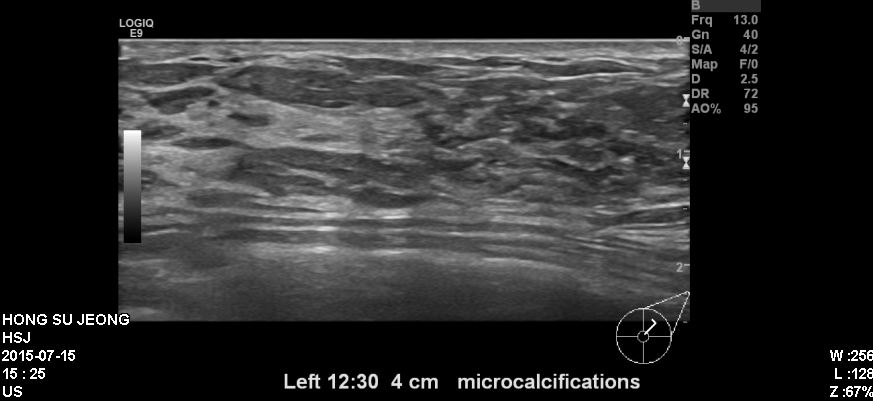

건진상 이상소견으로 내원하신 40대 환자분이십니다.

본원에서 유방초음파상 좌측 상내측과 상외측에 의심되는 혹 있어 조직검사 시행하였고

결과상 상피내암 진단되었습니다.